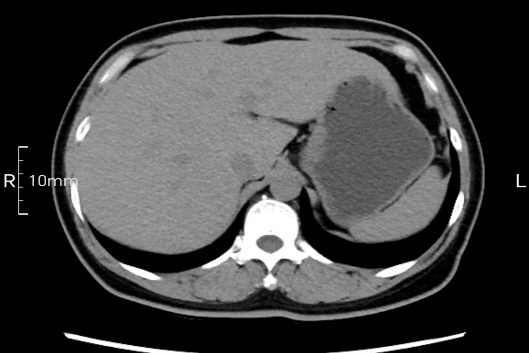

看看下面三幅便知遵醫囑的重要性。

禁食但檢查前沒有喝飽,胃未能漲開,胃壁觀察效果不佳。